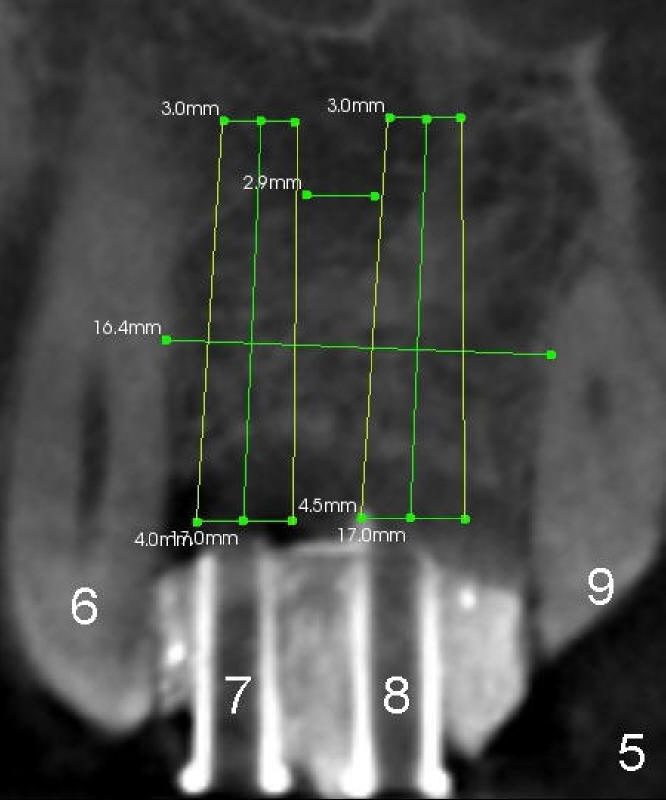

Gingival Graft?

Forty-five-year-old Spanish man has lost the teeth #7 and 8 for 2 years (due to caries, Fig.1,2) with localized buccal plate atrophy (Fig.1-3 *).  Wax-up (Fig.4) shows that implant supported crowns will look longer than their counterparts (#7,8 vs. 9,10).